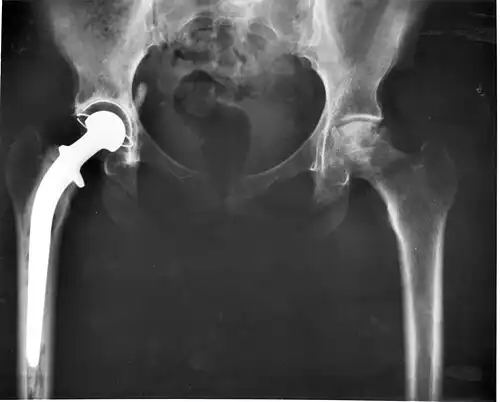

در پزشکی، بازسازی مفصل با ایجاد یک مفصل مصنوعی یا تغییر شکل دادن مفصل را مَفصَل سازی، تعویض مفصل یا آرتروپلاستی ( Arthroplasty ) می گویند.

مفصل سازی به معنی جایگزین کردن مفصل طبیعی آسیب دیده با یک مفصل مصنوعی یا کاذب است تا درد بیمار بهتر شده یا دامنه حرکتی مفصل بهبود یابد.

سه نوع مفصل سازی وجود دارد: برداشتن سطوح مفصلی، بازسازی با جاگذاری و تعویض مفصل با پروتز ( معمولاً فلزی ).

عمل جراحی مفصل سازی با پروتز به طور شایعی در زانو و استخوان ران کاربرد دارد. شایعترین علل آرتروز، روماتیسم مفصلی و بافت مردگی بی خونی هستند.